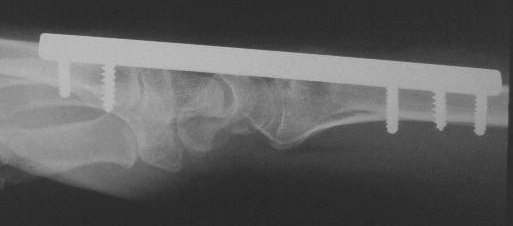

Clinical Example: Distraction plate fixation distal radius fracture

distal radius fracture

distraction plate